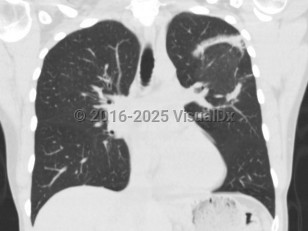

Patients typically present with relatively short duration of symptoms (weeks to months) including a persistent nonproductive cough, dyspnea, fever, malaise, weight loss, and occasionally other influenza-like symptoms (nasal congestion, headache, chills and sweats, sore throat, myalgia). Hemoptysis is uncommon. Physical examination reveals inspiratory crackles in a majority of patients, and radiographic findings include peripheral, patchy bilateral opacities.